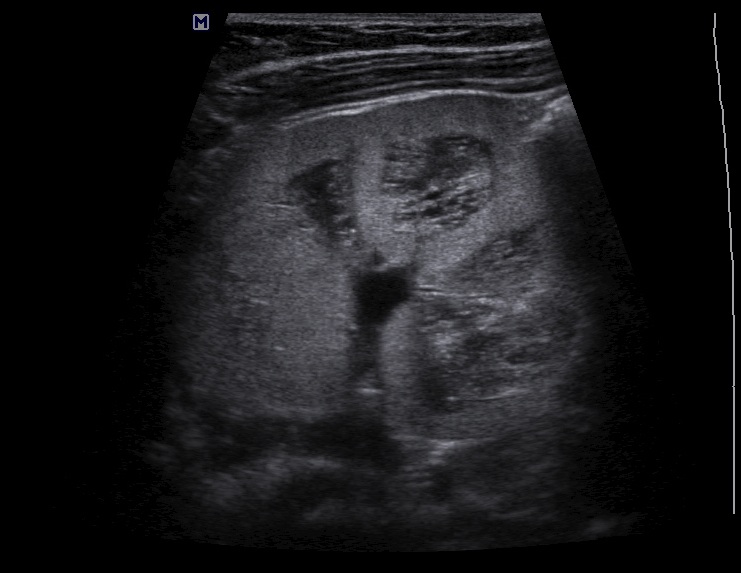

Осмотрен мной ребенок впервые, обращено внимание на большие почки, 90х40мм, паренхима 17-18мм, корковый слой гиперэхогенный, пирамидки дифференцируются. Линейным датчиком определяется: кисты или расширенные канальцы в пирамидках. Структура печени в 1 мес была не изменена, в н.в. отмечается перипортальный фиброз, размеры печени и селезенки увеличены.

Поставил медуллярную кистозную дисплазию, почитав литературу предполагаю нефронофтиз Фанкони, но к сожалению не нашел картинки только описание данной болезни. Поделитесь своим мнением.

структура линейным датчиком.jpg